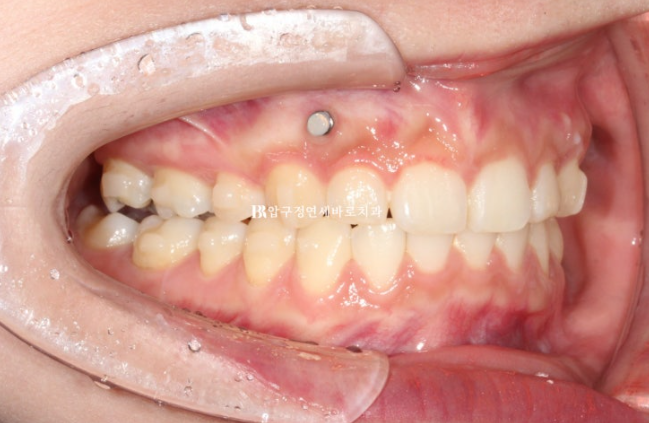

이때부터 거미스마일을 적극적으로 해소하기 위해서 앞니에 미니스크류를 심었고 고무줄을 함께 걸기 시작합니다.

23.07

재제작시 발치공간은 절반정도 남은 상황이였습니다.

24년 7월까지 1년 간 첫번째 추가장치를 다 낀 후 모습입니다.

24.07

과개교합은 해결되고 발치공간은 대부분 사라졌지만 여전히 중심선이 미세하게 안 맞고

발치공간에 미세한 틈이 있으며

어금니 교합이 뜨는 부분이 있어서 재제작을 한 번 더 했습니다.